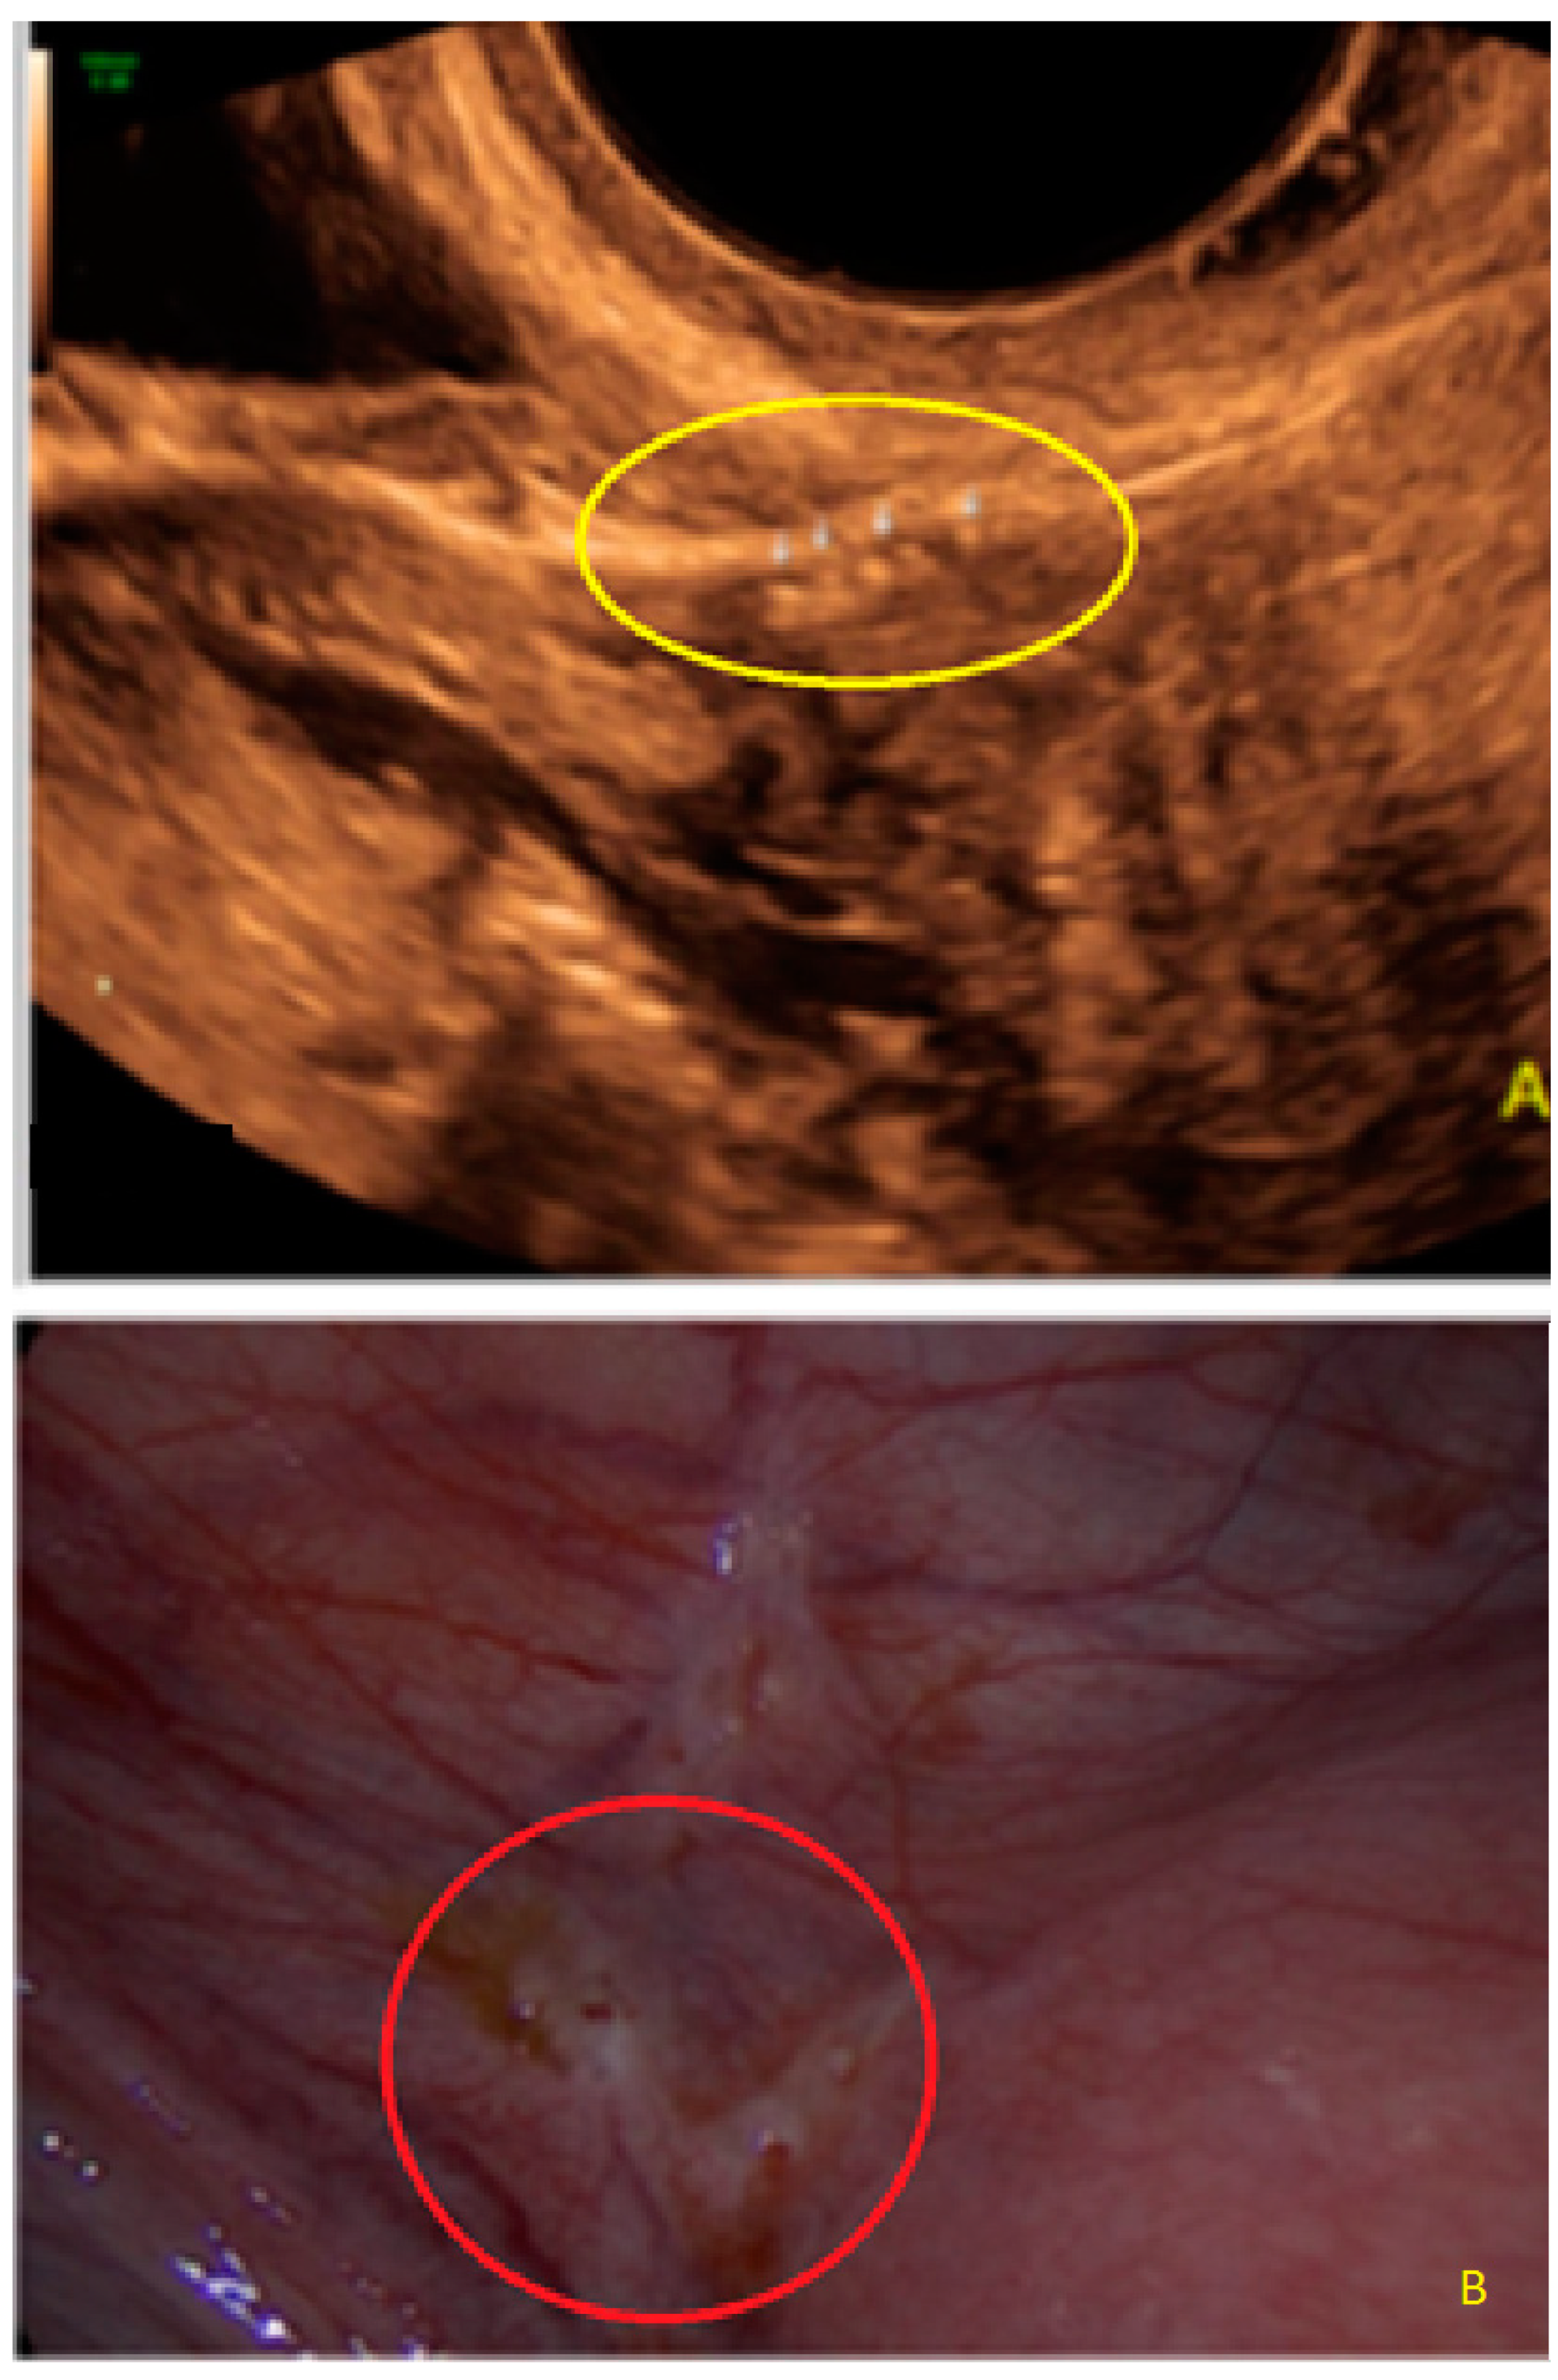

- The presence of hypoechogenic associated tissue (hypoechoic areas surrounding a small cyst area; we called this a “hat”). This tissue does not protrude or invaginate the peritoneal surface.

- The lesion may be convex, protruding from the peritoneal surface into the peritoneal cavity (we called this “bulging”), or it may appear as a concave defect in the peritoneum (we called this a “pocket”).

- The presence of hyperechoic foci (we called this a “pearl”).

3.2. Cystic Multiple Separate Lesions